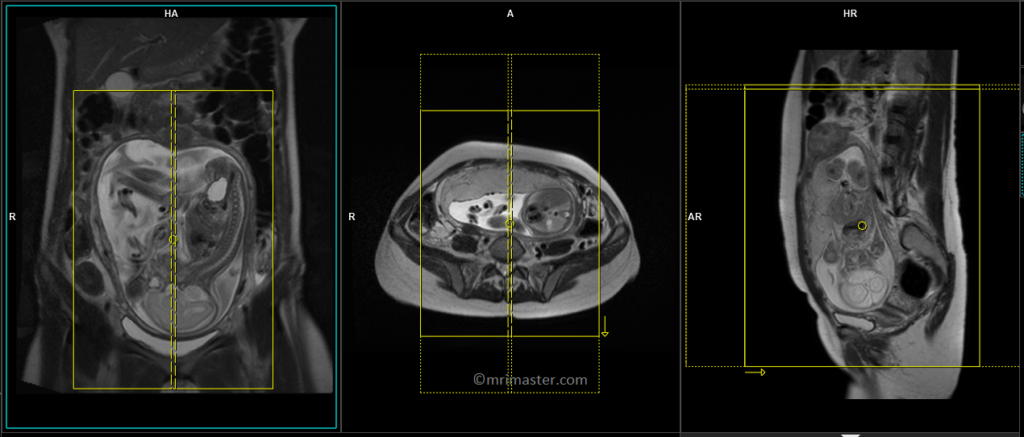

T2 HASTE sagittal 6 mm Respiratory gated

Begin by planning the sagittal slices on the coronal localizer and position the block parallel to the gravid uterus. Verify the positioning block in the other two planes to confirm proper alignment. It is essential to provide an appropriate angle in the axial plane, which should be perpendicular to the gravid uterus. The number of slices should be sufficient to cover the entire abdomen and pelvis, from right to left. The field of view (FOV) must be wide enough to encompass the whole abdomen and pelvis, typically ranging from 400 mm to 480 mm. However, it is important to note that these scans usually take approximately 35 to 40 seconds, which can be challenging for a pregnant woman to hold her breath. To address this issue, we perform the scan under respiratory gating. There are two options for respiratory gating: the liver dome method or the table respiratory sensors. In our department, we utilize the table respiratory sensor.

T2 HASTE coronal 6 mm Respiratory gated

Plan the coronal slices on the sagittal localizer and position the block parallel to the gravid uterus. Verify the positioning block in the other two planes for proper alignment. An appropriate angle should be set in the axial plane, running parallel across the gravid uterus. The number of slices should be sufficient to cover the entire abdomen and pelvis, from the anterior abdominal wall to the spinous process of the vertebrae. The field of view (FOV) must be large enough to encompass the entire abdomen and pelvis, typically ranging from 400 mm to 480 mm. However, it is important to note that these scans usually take approximately 30 to 35 seconds, which can be challenging for a pregnant woman to hold her breath. To address this issue, we perform the scan under respiratory gating. There are two options for respiratory gating: the liver dome method or the table respiratory sensors. In our department, we utilize the table respiratory sensor.

T2 HASTE axial 6 mm Respiratory gated

Plan the axial slices on the sagittal scans and angle the position block perpendicular through the gravid uterus. Verify the positioning block in the other two planes for proper alignment. An appropriate angle should be set in the coronal plane, running perpendicular across the gravid uterus. The number of slices should be sufficient to cover the entire abdomen and pelvis, from the diaphragm to the pubic symphysis. The field of view (FOV) must be large enough to encompass the entire abdomen and pelvis, typically ranging from 400 mm to 480 mm. However, it is important to note that these scans usually take approximately 40 to 45 seconds, which can be challenging for a pregnant woman to hold her breath. To address this issue, we perform the scan under respiratory gating. There are two options for respiratory gating: the liver dome method or the table respiratory sensors. In our department, we utilize the table respiratory sensor.